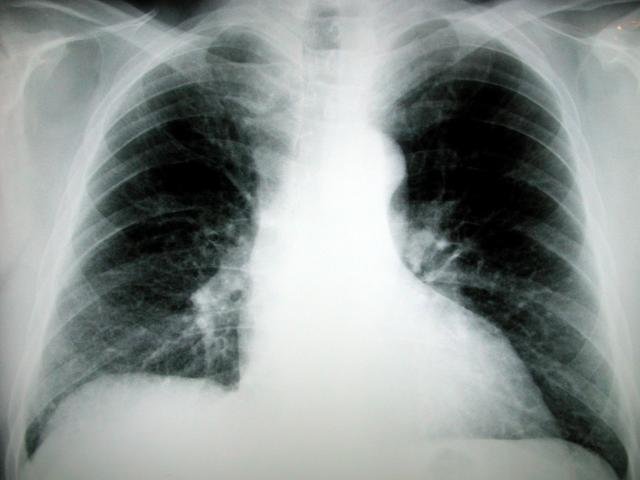

Больницы и поликлиники города в этом году пополнятся новыми рентген - диагностическими комплексами и мобильными рентгеновскими аппаратами. Приобретение нового оборудования осуществляется в рамках муниципальной целевой программы "Оснащение муниципальных учреждений здравоохранения города Владивостока рентгенологическим оборудованием" на 2010-2012 годы.

В этом году планируется закупить телеуправляемые рентген-комплексы в городские клинические больницы №1 и №4, цифровые рентген-комплексы в ГКБ №2 и в детскую клиническую больницу №3, а также пленочные рентген-комплексы в поликлиники №3 и №8.

"Программа рассчитана на три года и главная ее цель - заменить старое рентген-оборудование, работающее по 15, 20 лет на новое, современное, - подчеркнул глава города Игорь Пушкарёв, - первый этап программы успешно пройден. В 2010 году в городскую клиническую больницу №1 была закуплена скопическая приставка, позволяющая проводить рентген-диагностику органов желудочно-кишечного тракта и пищевода. В городскую больницу №3 приобретен рентгенологический комплекс с приставкой для томографии. В городскую клиническую инфекционную больницу №1 поступил мобильный рентгеновский аппарат. В поликлиники №3, №5, №8 и №10 поступили новые цифровые флюорографы. В ГКБ №2 закупили новый цифровой телеуправляемый рентгенологический комплекс. Теперь врачи должны повышать качество медицинских услуг, потому что у них для этого есть все необходимое".